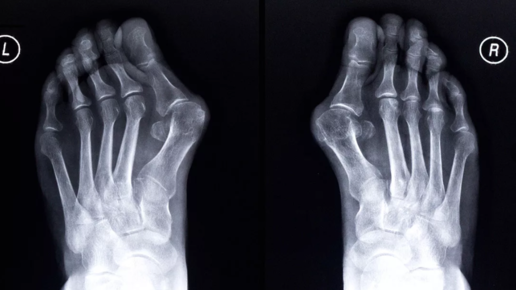

Удаление косточек на ногах: в каких случаях поможет обычное лечение, а когда результат даст только операция. Косточка – нарост возле основания большого пальца стопы. В медицинской терминологии это – вальгусное искривление стопы. Ведь происходит не образование нароста, а палец меняет угол своего наклона, стопа теряет свою анатомическую форму. Это не только некрасиво, но и чревато утерей возможности передвигаться самостоятельно. Чтобы этого не произошло, необходимо удаление косточек на ногах. Сделать это можно двумя путями – при помощи консервативного лечения или операции...